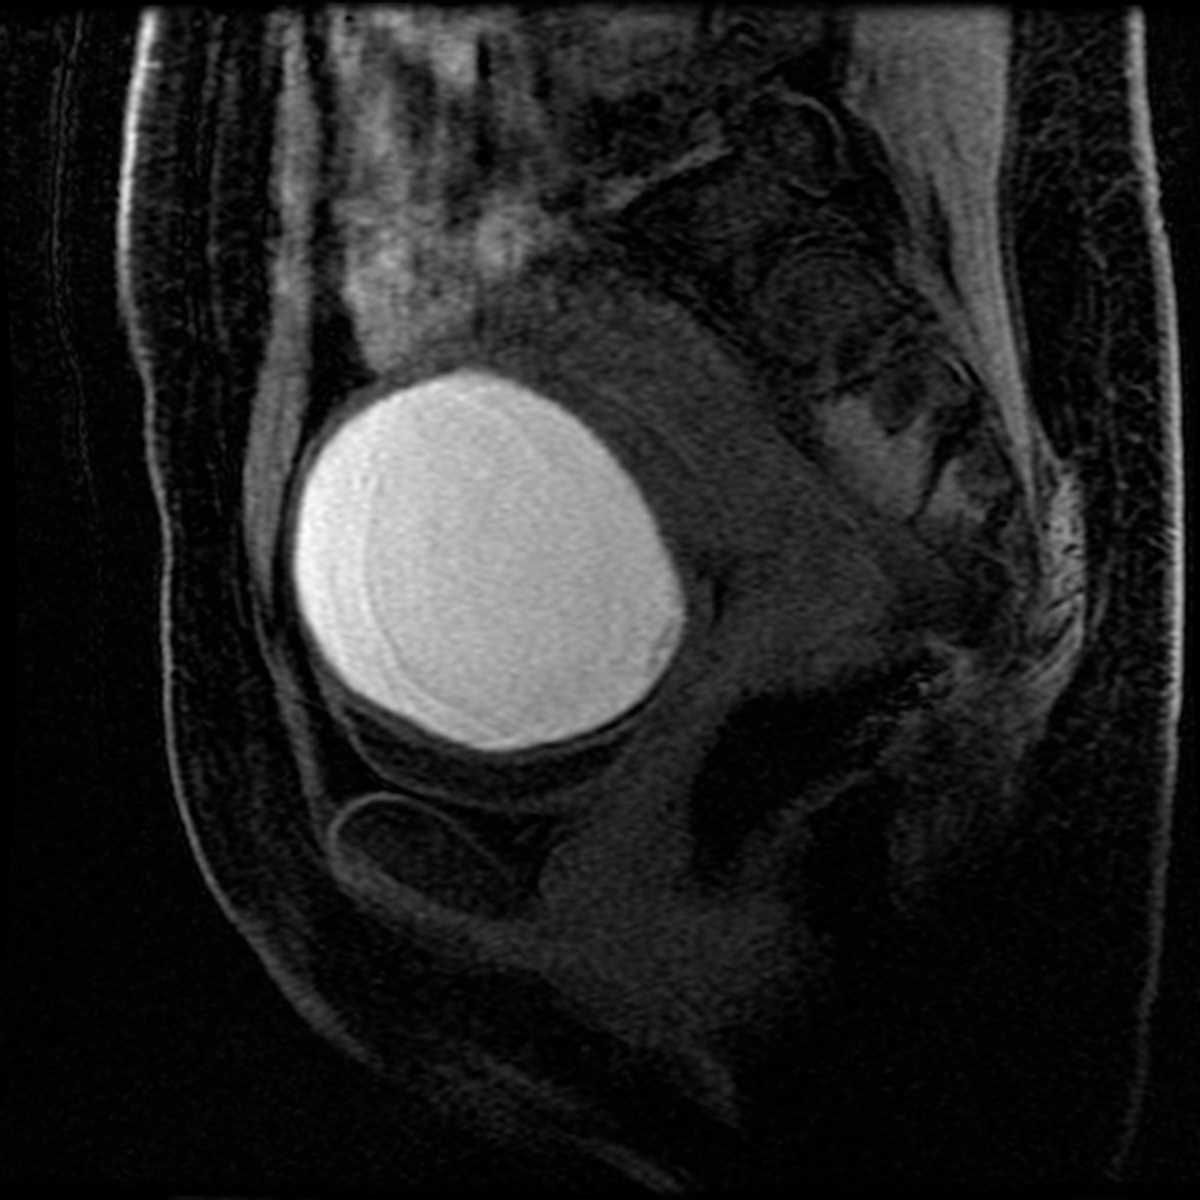

Type I choledochal cyst

MRI images demonstrates characteristic fusiform dilatation of the CBD in a type I choledochal cyst.